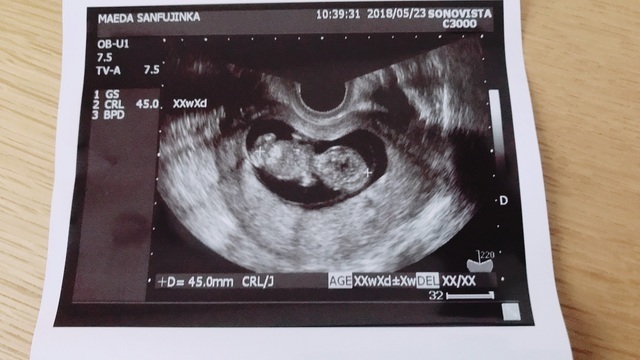

11週0日(11w0d・性別不明)|sumire0113 さん(35歳)

エコー写真撮影時のエピソード:

九州から関東への引越し後初めて新しい病院で撮ったエコー写真です。

今までのエコーから腹部エコーに初めて変わり、先生も大笑いするくらいに、ぐるんぐるんと動き回っている姿を見て感動しました。

まだつわり真っ只中だったので、これでまだ頑張れると勇気をもらいました。 そんな我が子、エコー写真を撮る瞬間にピースをしてくれた瞬間です。